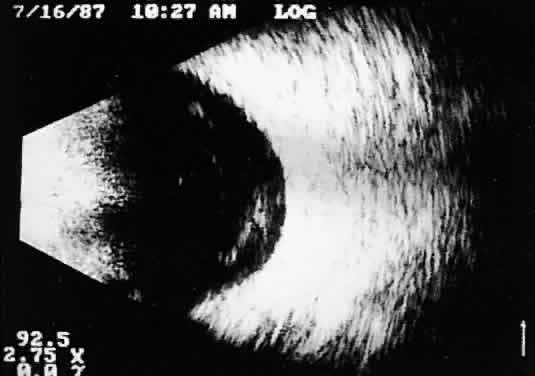

Fig. 5. Contact B-scans. A. Heavy formed vitreous hemorrhage obscuring choroidal mass. B. Voluntary movement of the globe causes the formed vitreous to shift, permitting easy detection of the ocular wall mass.